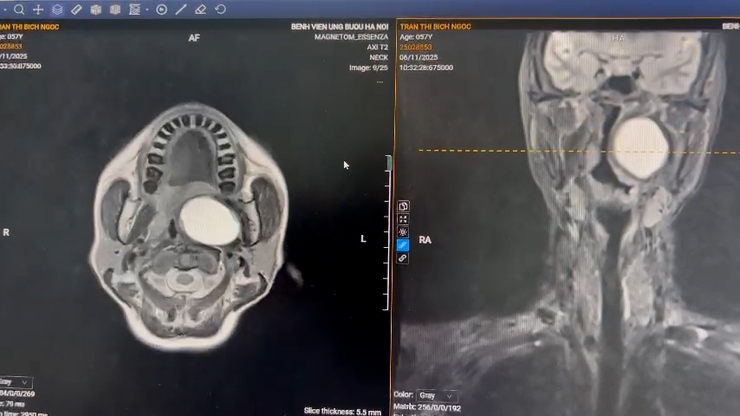

Hình ảnh khối u đẩy lệch trái trên phim chụp CT.

Bệnh nhân T.B.N. đến bệnh viện trong tình trạng khó chịu, nuốt vướng, có khối vùng cổ bên đẩy lồi thành bên họng và khẩu cái mềm bên trái kích thước khoảng 6 × 5 cm, mềm, bề mặt niêm mạc nhẵn, không loét. Qua thăm khám, các bác sĩ phát hiện u thành bên họng trái, tăng sinh mạch nhiều, gợi ý khối u phát triển sâu vào khoang bên họng miệng. Đây là vị trí giải phẫu hẹp, gần động tĩnh mạch cảnh trong và các dây thần kinh vùng nền sọ (dây thần kinh số 9,10) đòi hỏi bác sĩ phải lựa chọn phương pháp phẫu thuật ít xâm lấn, đảm bảo phẫu trường rõ ràng và an toàn.